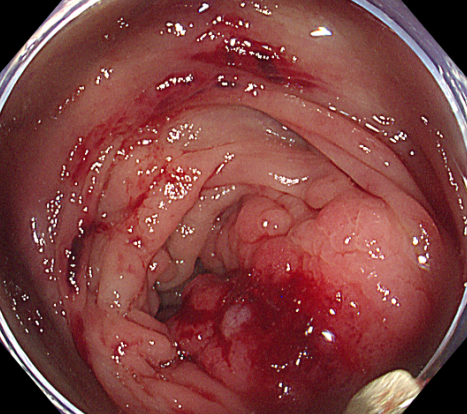

导管置入术后 3 天,患者腹痛明显缓解,能少量进食流质食物,体重也略有回升。此时结肠镜检查进一步明确:结肠脾区存在直径约 10 cm 的肿瘤,正是导致结肠梗阻的「元凶」。「时机成熟了,可以手术!」李森主任斩钉截铁地说。

手术当天,在麻醉科团队的严密监测下,李森主任带领赵本和主任、吴兵主治医师团队小心翼翼分离粘连组织,先精准定位肿瘤边界,再依次切除胰体尾、脾脏、受侵犯的部分小肠及结肠脾区肿瘤。最关键的环节是消化道重建:团队需同时完成食管空肠吻合、结肠对端吻合,确保术后消化道功能能正常运转。